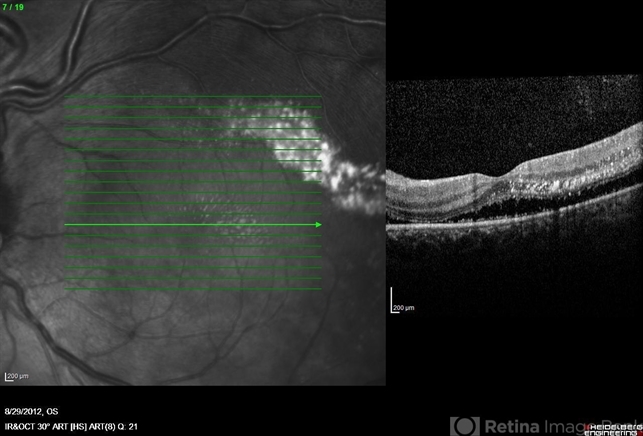

- Heidelberg Spectralis

- OCT image of the left eye of a 25-year-old woman with exudative retinal detachment secondary to retinal angiomatosis (Von Hippel-Lindau).